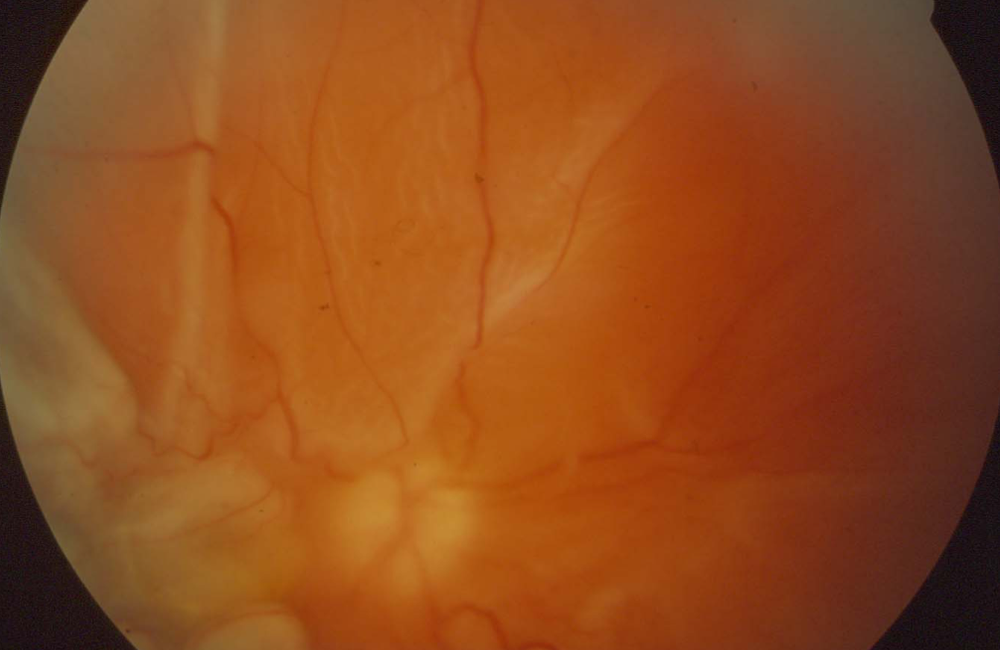

What does this show?

Who does it occur spontaneously in?

What causes this to occur as a result of trauma?

Retinal detachment

Occurs spontaneously in short-sighted people mostly

Fluid under the retina in trauma causes it to detach